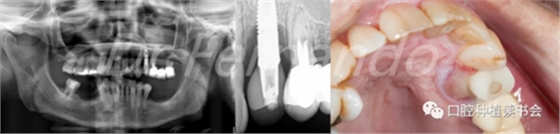

患者為64歲女性,大約在5年前在24位點植入種植體,近期感覺種植體有疼痛不適,相應(yīng)的上腭部位有明顯的病變(圖 19-右 )。

圖19 24種植位點腭側(cè)可見明顯腫脹,X片顯示明顯骨吸收

完成影像診斷檢查(曲面斷層和根尖X片)后,我們發(fā)現(xiàn)24種植位點存在很大的骨缺損,大約為種植體長度的40%(圖19-左),探診深度大于6 mm。